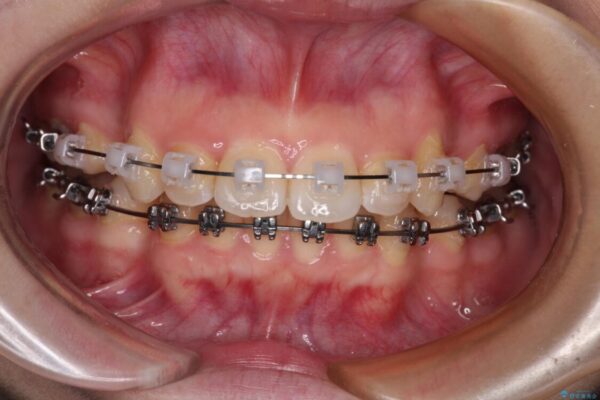

治療途中

• 【モニター】口が閉じられない ワイヤー装置での抜歯矯正 治療途中画像

上下前歯が著しく前突している状態であったので、上下左右の第1小臼歯4本を抜歯し、ワイヤー装置にて矯正治療を行うこととしました。

舌の突出癖により、前突になったと考えられたため、舌のトレーニングをしっかりと行うよう指導しました。

※写真にある上顎装置はメタルブラケットではありません。メーカー在庫都合などにより別の装置を使用しております。